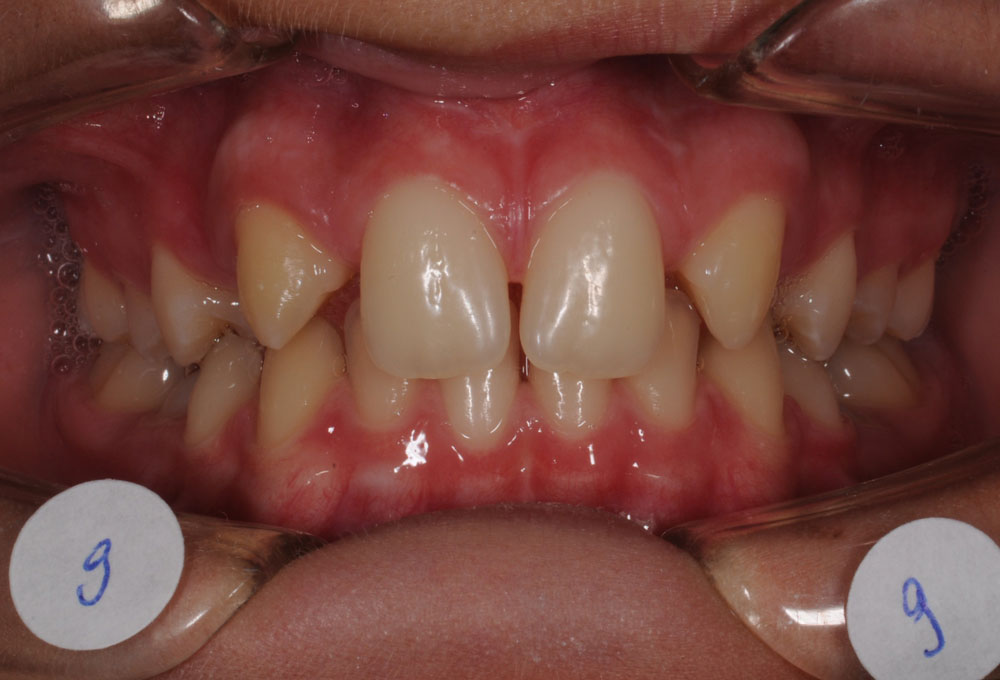

In genere le agenesie dentarie si manifestano con presenza di spazi interdentali.

Le opzioni terapeutiche ortodontiche si possono sintetizzare in:

Il vantaggio principale di questa soluzione è che si può ottenere una buona estetica del sorriso e una corretta funzione masticatoria senza ricorrere a sostituzioni protesiche.

Frequentemente, in questi casi si ricorrere a una finalizzazione estetica con rimodellamento della forma di alcuni elementi dentali (camouflage), per meglio inserirli nel contesto estetico e funzionale orale.